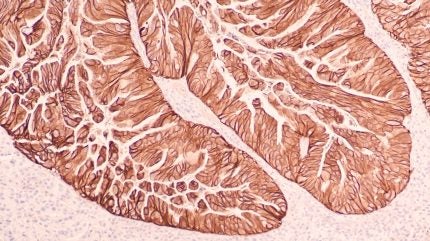

Daiichi Sankyo and AstraZeneca’s Enhertu (trastuzumab deruxtecan) has received approval from China’s National Medical Products Administration (NMPA) for adults with locally advanced or metastatic human epidermal growth factor receptor 2 (HER2) positive gastric or gastroesophageal junction (GEJ) adenocarcinoma.

Enhertu is a specifically engineered HER2-directed DXd antibody drug conjugate discovered by Daiichi Sankyo and jointly developed with AstraZeneca.

In DESTINY-Gastric04, Enhertu showed a 30% reduction in risk of death against ramucirumab plus paclitaxel for second-line HER2-positive unresectable or metastatic gastric or GEJ adenocarcinoma. Median overall survival was 14.7 months with Enhertu versus 11.4 months for the comparator group.

Progression-free survival analysis indicated a 26% lower risk of disease progression or death with Enhertu. Confirmed objective response rate was 44.3% for Enhertu, with seven complete responses and 97 partial responses.